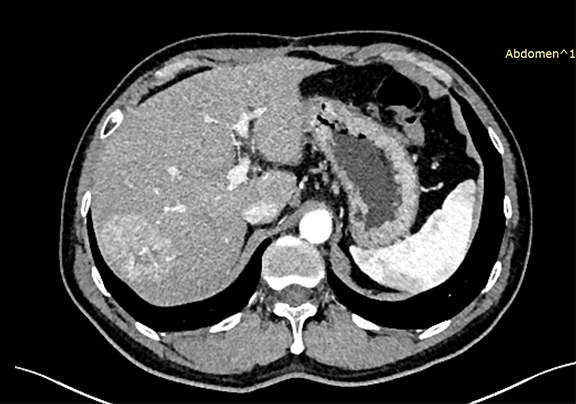

下腹部增强CT示:符合肝脏术后改变,请结合临床;肝右叶占位性病变,考虑肝Ca 可能性大。

术前CT检查:

静脉期